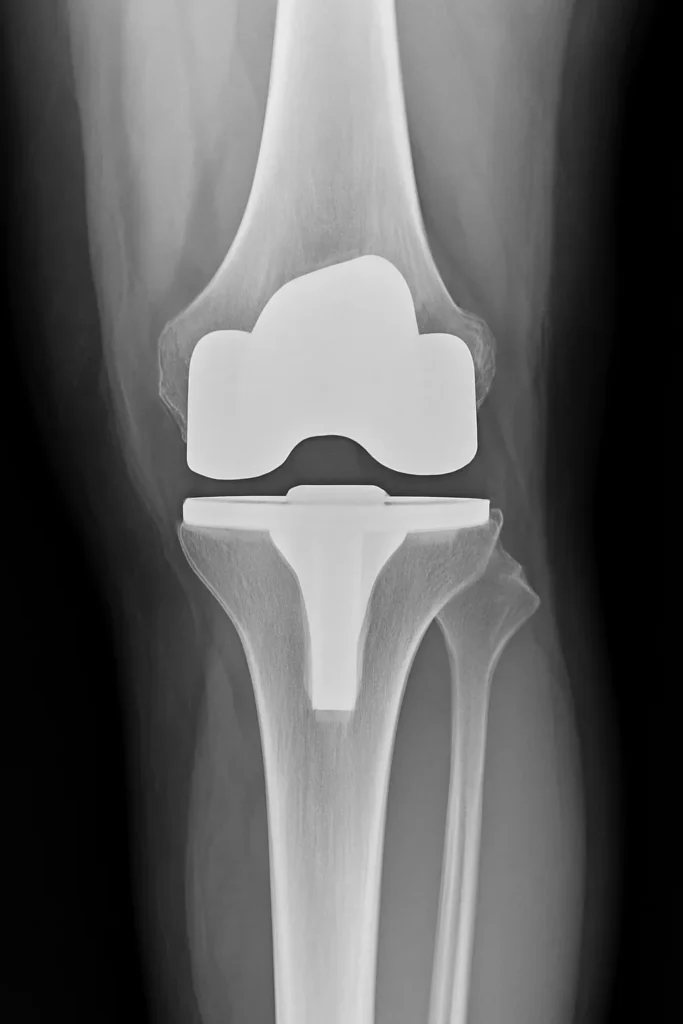

Ha azonban a porc már nagyrészt elkopott, a mindennapi tevékenységek jelentősen korlátozottak, és a konzervatív módszerek nem hoznak megfelelő javulást, felmerül a térdprotézis beültetés. Ilyenkor a károsodott ízfelszíneket speciális, fém és műanyag komponensekből álló implantátumokkal helyettesítik. A beavatkozás lehet részleges, amikor csak az ízület egy meghatározott rekesze kerül pótlásra, vagy teljes, amikor a térd mindhárom fő ízületi felszínét cserélik.